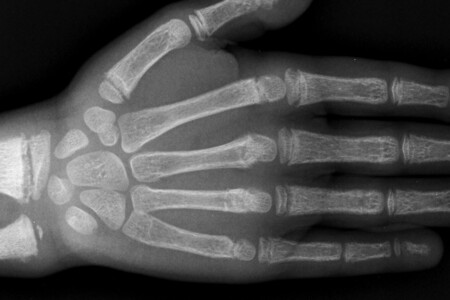

Pro diagnostiku SARS je kromě přítomných příznaků příznačné rentgenologické vyšetření hrudníku a rozhodující je i údaj o pobytu v postižené oblasti či kontakt s osobou postiženou SARS. Také je třeba odebrat krev na laboratorní vyšetření. V léčbě se uplatňují protivirové léky a kortikoidy, které zlepšují tíži příznaků. V roce 2004 byla vyvinuta vakcína. V té době již SARS vymizel, takže její účinnost na širší spektrum pacientů nebyla prakticky vyzkoušena. Preventivním opatřením je především izolace nemocných a podezřelých osob, jelikož se infekce rychle šíří. Lidé, kteří byli v kontaktu s nemocnými, musí být 10 dní v karanténě.